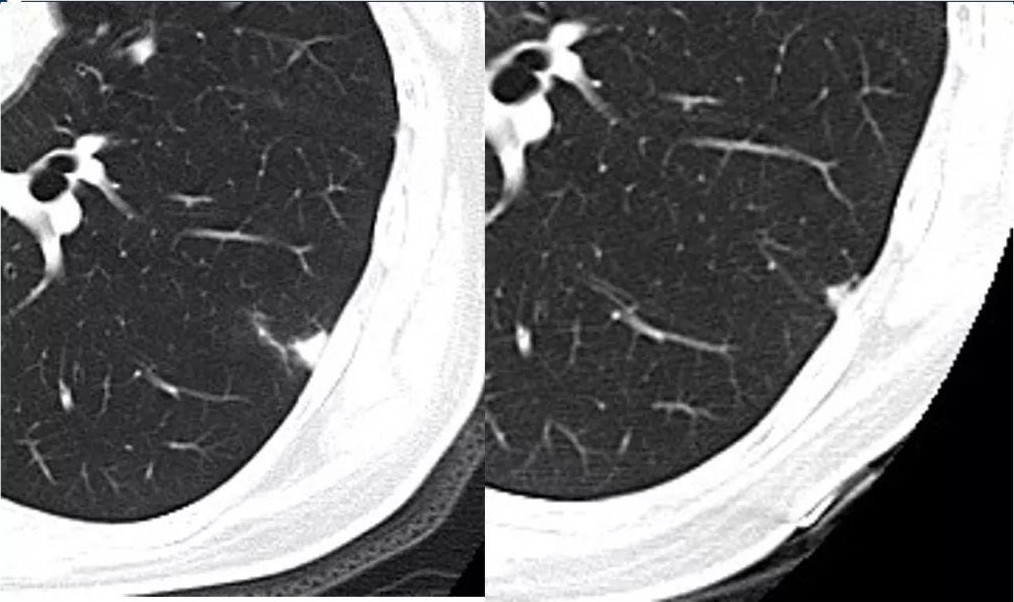

(图为肺结节在随访观察中的变化,其中A图为基线,B图为三个月后,C图为六个月后,该患者术后病理为浸润性腺癌)